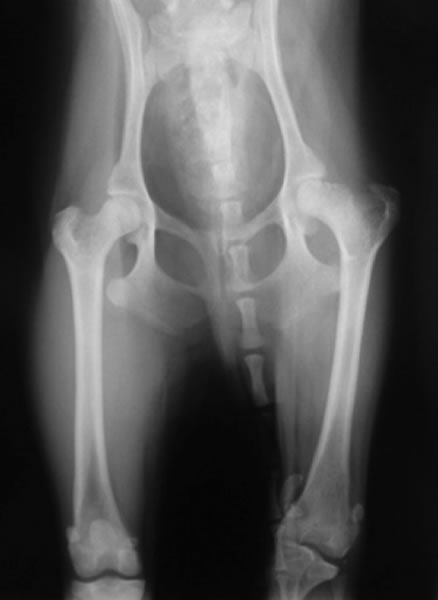

後足には、上に位置する関節から順に股関節、膝関節、足根関節の3つの関節があります。なかでも、ワンちゃんの跛行の約50パーセントは膝関節が原因で生じているといわれています。膝関節では特に前十字靭帯断裂症、膝蓋骨脱臼の発生が多いです。関節に発生した病気によって、関節内で炎症が起こり、痛みが生じます。痛みが生じると跛行するようになります。跛行が見られた場合、できるだけ早く診断し治療をおこなうことが重要です。

成長過程で股関節(寛骨と大腿骨)の発育異常が生じ、股関節に緩みが引き起こされる疾患です。緩みのある不安定な股関節を動かすことで、関節の軟骨部分が損傷を受け関節炎がはじまります。関節炎による痛みから跛行を呈します。

ラブラドール、ゴールデン、バーニーズ、シェパード、ニューファンなどの大型~超大型犬で多い。柴犬、ポメラニアン、トイプードルなどの中型、小型犬でも起こります。